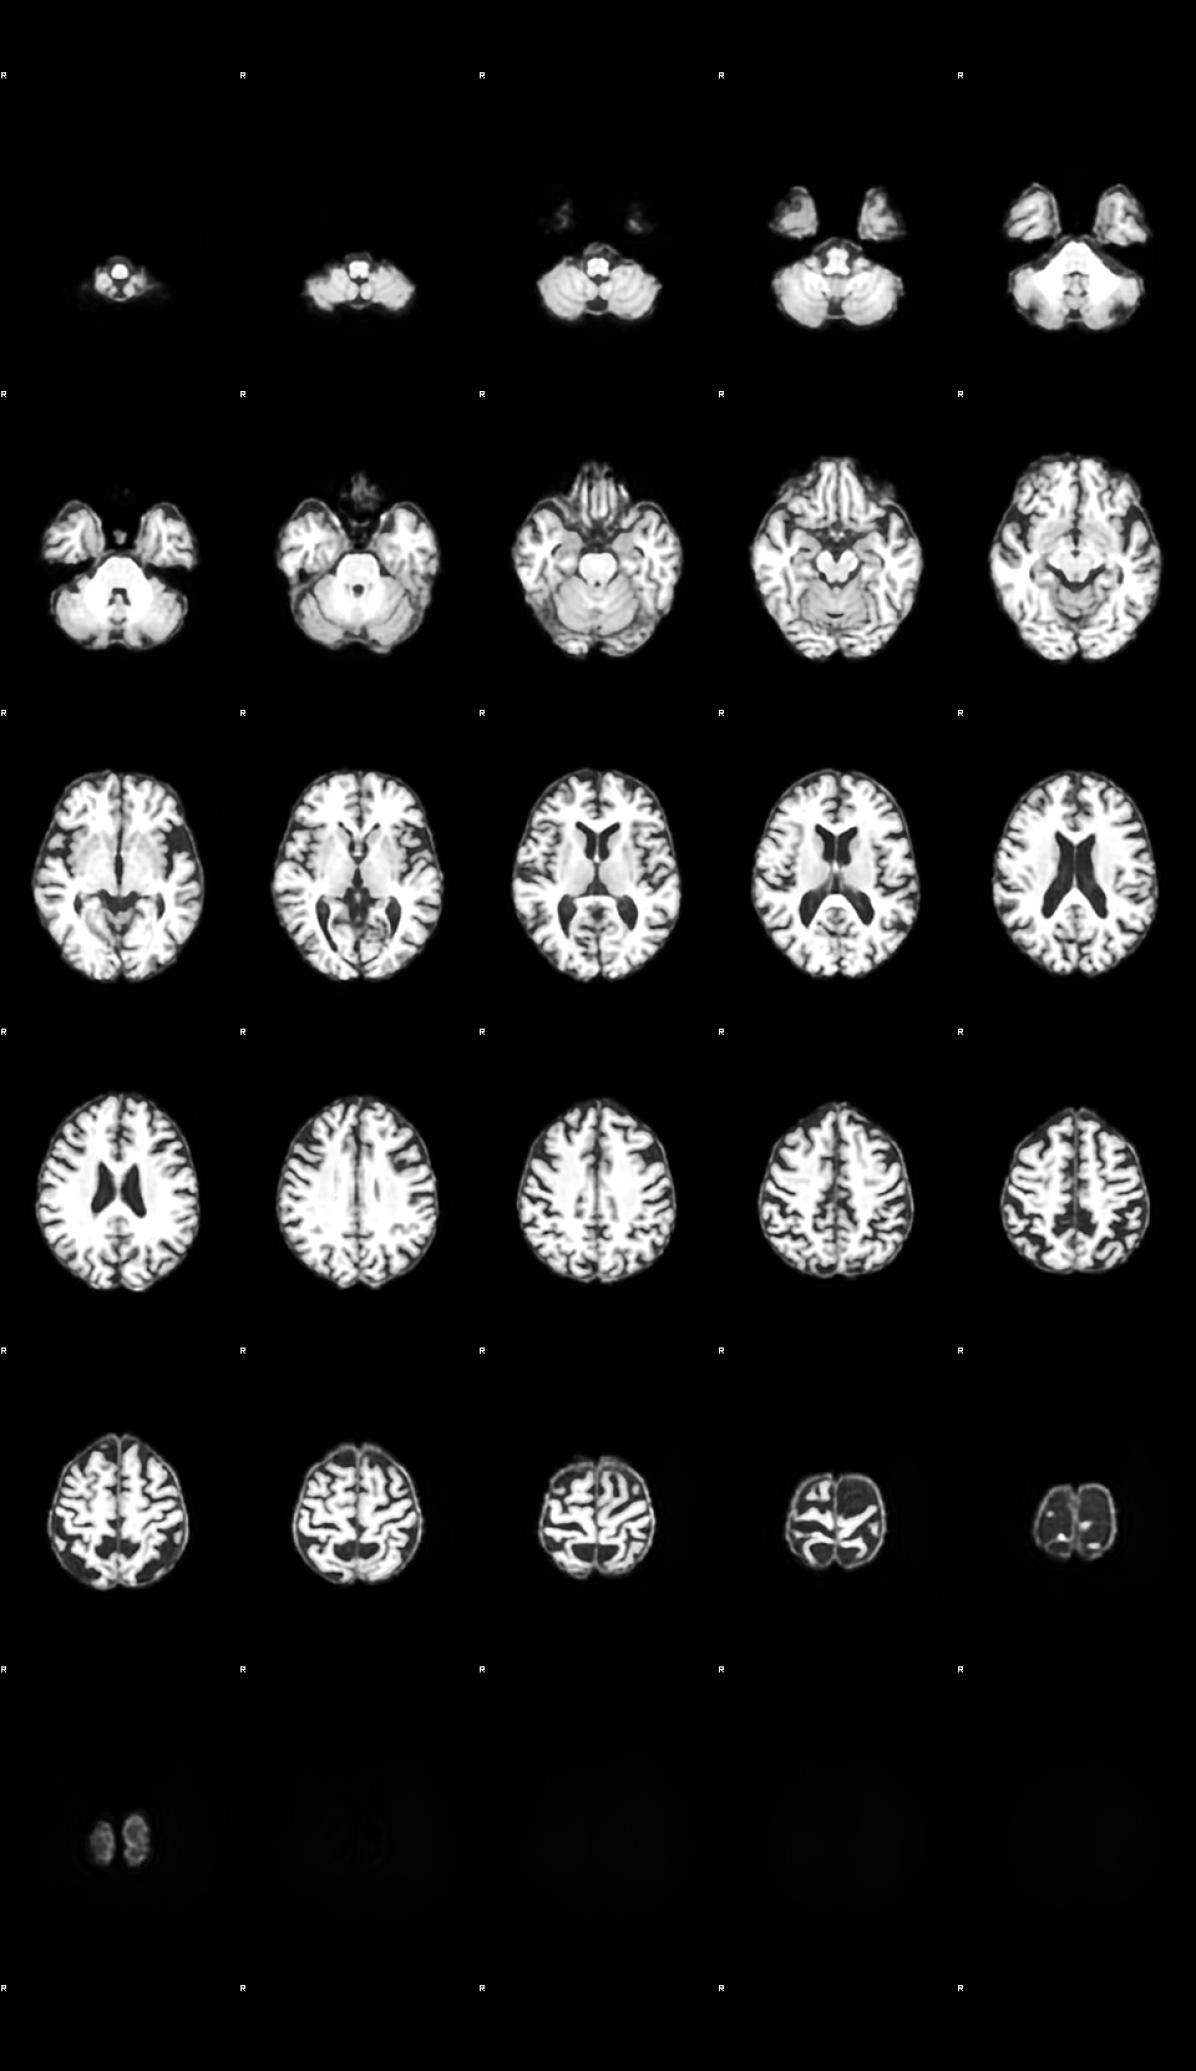

Refer to caption

Figure 2: Comparison of a random reconstruction across the pathological training modes. α𝛼\alpha-WGAN’s reconstruction was upsamled to 1mm isotropic.

Table 1 details the quantitative results on image reconstruction fidelity. To provide comparison with [Kwon et al.(2019)Kwon, Han, and Kim] we have measured Maximum Mean Discrepancy (MMD) [Gretton et al.(2012)Gretton, Borgwardt, Rasch, Schölkopf, and Smola] and Multi-Scale Structural Similarity (MS-SSIM) [Wang et al.(2003)Wang, Simoncelli, and Bovik]. Significant improvements in fidelity were observed with the proposed method, both at 3mm and full resolution. We measured Dice [Milletari et al.(2016)Milletari, Navab, and Ahmadi] overlap between segmentations of Gray Mater (GM) and White Matter (WM) in the ground truth and reconstructed volumes, and Cerebrospinal Fluid (CSF) as a proxy to the neuromorphological correctness of the reconstructions. The segmentations were extracted from the unified normalisation and segmentation step of Voxel Based Morphometry (VBM) [Ashburner and Friston(2000)] pipeline of Statistical Parametric Mapping [Penny et al.(2011)Penny, Friston, Ashburner, Kiebel, and Nichols] version 12. All metrics have been calculated over the test cases. Again, the proposed methods achieved statistically-significant (p<0.01𝑝0.01p<0.01 Wilcoxon signed rank test) improved Dice scores against the α𝛼\alpha-WGAN baseline, interchangeably between the Baur and Adaptive loss function.

It can clearly be seen that our VQ-VAE model combined with the 3D Adaptive loss achieves the best performance in all three training modes. Interestingly the Bau r loss trained model consistently performs better on MS-SSIM then the adaptive one. This might be attributed to the fact that the reconstructions of the adaptive appear like they have been passed through a total variation (TV) filter [Rudin et al.(1992)Rudin, Osher, and Fatemi] which could interfere with the fine texture of white matter. This indicates the need for future research in a hybrid loss function that is able to work better at a texture level, possibly combining the adaptive loss with image gradient losses. Even though the die scores are excellent which indicates possible good neuromorphometry, we would like to refer the reader to the VBM analysis that follows for a more in depth analysis since the SPM implementation is known to be highly robust.

Lastly, in Figure 4, we looked at the T-test maps between AD and HC patients at the original resolution using the original data (labeled in the figure as ground truth) and then again using the reconstructed data for each method. In contrast to Figure 3, the best performing model is the VQ-VAE with Adaptive loss, where similar T-map clusters are observed, with low t-map residuals throughout. This means the proposed VQ-VAE Adaptive model was able to better learn the population statistics even though the MS-SSIM was found to be marginally lower when compared with the VQ-VAE with Baur loss. The discrepancy might be due to structural nature of the brain which is enforced by the sharper boundaries between the tissues of the TV filter like reconstructions in comparison with the more blurrier VQ-VAE Baur based output as seen in Figure 2.